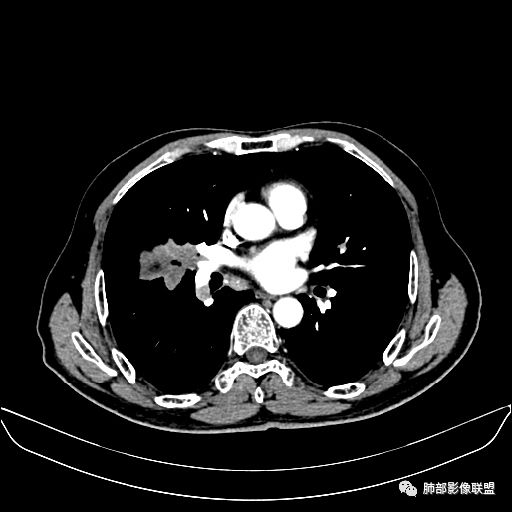

住院4天后行胸部增强CT

动脉期

老年男性,因“咳嗽咳痰1月余。”入院。病程中咳嗽咳痰,咳黄白痰,间断咯少许鲜红色痰血。PPD阳性。胸CT:右肺中叶外侧段支气管管腔阻塞,大片实性病变,病灶边缘光滑,部分边缘膨隆,可见分叶,肺门及纵隔可见肿大淋巴结,并可见钙化。增强可见病灶明显强化,而且延迟强化明显,病灶内多发低密度区,内见血管影,血管变细、部分血管破坏。考虑恶性病变可能性大,鉴别慢性肉芽肿性病变。

胸CT:跨叶大肿块,主体在中叶,右中叶外侧段支气管阻塞,病灶部分边缘膨隆,可见分叶,部分边缘平直,肺门及纵隔可见肿大淋巴结。增强病灶不均匀强化,延迟强化明显,病灶内多发低密度区,内见血管飘浮,部分血管变细、模糊。考虑:恶性病变可能性大,大细胞?淋巴瘤?鉴别慢性肉芽肿性病变。

右肺中叶软组织肿块,外围向内生长,叶间胸膜向前内移位,肿块近肺门侧跨叶,中叶外侧段支气管截断,密度不均匀,双侧肺门及隆突下见肿大淋巴结,增强后呈中度不均质强化,肺动脉供血,多发坏死区,边界尚清,坏死区域内见结构,结合病史考虑恶性,鉴别诊断1结核,爬行征是沿支气管树分布,外宽,内窄,周围有卫星灶,内气管狭窄后扩张,此例沿叶间胸膜长轴分布,气管有截断,不典型。2炎性肉芽肿,符合的地方下方层面增强后延迟性轻度环形强化,不符临床无发热等急性感染病史,实验室指标不符,病灶周围渗出及慢性炎性改变有,不明显。